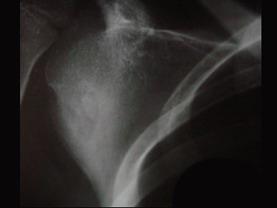

问题 患者,男,34岁,6个月前劳累后出现右肩部疼痛不适,休息后可缓解,曾服用消炎药,对症治疗,效果不佳,实验室检查正常,请结合所提供的图像,选择最佳选项 ( )

选项 A、良性骨母细胞瘤 B、骨样骨瘤 C、骨梅毒 D、骨髓炎 E、右股骨骨纤维异常增殖症

答案 B